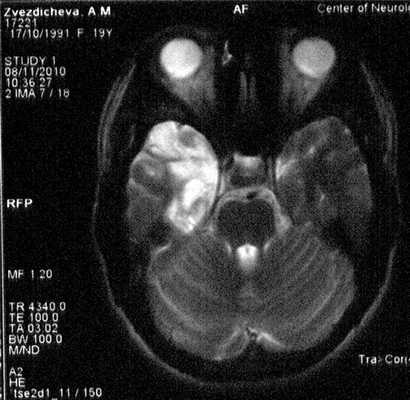

При МРТ-исследовании от 08.11.10 сохраняются поствоспалительные изменения в обоих полушариях большого мозга (рис. 3). Рисунок 3. МРТ пациентки З., аксиальное изображение.

На МРТ от 28.11.08 отмечена положительная динамика по сравнению с предшествующим исследованием (от 28.08.08) в виде уменьшения измененного МР-сигнала в правом полушарии большого мозга и отсутствия признаков объемного воздействия.

На 34-й день болезни (28.08.08) магнитно-резонансная томография (МРТ) головного мозга выявила в височной доле, островке, наружных отделах подкорковых структур, медиальных отделах лобной доли, частично теменной доли и зрительном бугре правого полушария диффузную зону измененного сигнала, гиперинтенсивного в режимах Т2 и T2 diff и гипоинтенсивного в режиме Т1; признаки объемного воздействия в виде слабой визуализации субарахноидального пространства височной доли и нижнего рога правого бокового желудочка; слева в медиальных отделах височной доли и островке выявлялась небольшая зона аналогично измененного MP-сигнала. Заключение: картина соответствует воспалительным изменениям в обоих полушариях головного мозга (рис. 2). Рисунок 2. МРТ больной З. на 34-й день болезни, аксиальное (а) и сагиттальное (б) изображения. Описание в тексте.